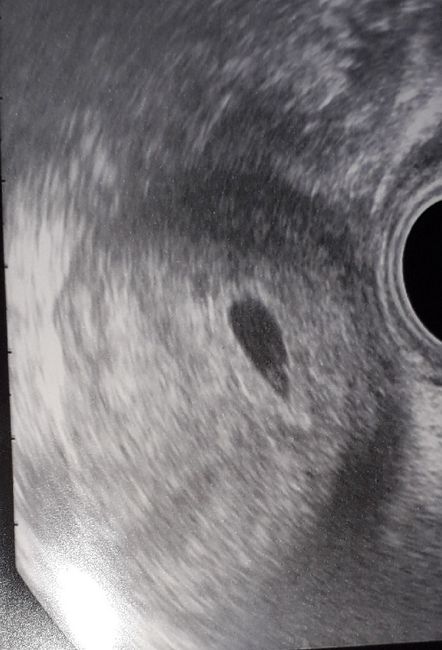

Buongiornooo.. stamattina è stato bellissimo 😍😍.. sono andata con mio marito .. il 5 devo ritornare .. troppo bello, non vedo l'ora .. il solo pensiero che sta benissimo mi riempie il cuore di gioia ..